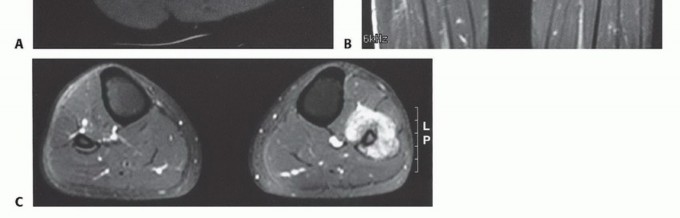

الدراسات التصويرية

تُعد الدراسات التصويرية حجر الزاوية في تشخيص أورام الشظية وتحديد مرحلتها:

- الأشعة السينية العادية (Plain Radiographs): تُظهر الأشعة السينية مدى تدمير العظم، ومدى انتشار الورم داخل العظم، وأي اختراق للقشرة العظمية.

- التصوير المقطعي المحوسب (Computed Tomography - CT): يوفر التصوير المقطعي صورًا تفصيلية للعظم، مما يساعد في تقييم مدى تدمير العظم وانتشاره داخل نخاع العظم. كما أنه مفيد لتقييم امتداد الورم إلى الأنسجة الرخوة المحيطة.

- التصوير بالرنين المغناطيسي (Magnetic Resonance Imaging - MRI): يُعد التصوير بالرنين المغناطيسي الأداة الأفضل لتقييم امتداد الورم إلى الأنسجة الرخوة المحيطة، وتحديد علاقته بالأعصاب والأوعية الدموية، وتقدير حجم الورم بدقة. كما أنه يوضح الامتداد داخل نخاع العظم بشكل ممتاز.